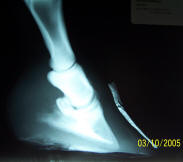

Miserably

lame Quarter Horse. P3 is penetrating the sole, with extensive sub-solar

abscessing. |

At 6

months, still room for improvement, but completely sound. |

After these radiographs were

taken, he was moved to a new home with no grass and lots of work to do.

He is now living in a heard, happily giving riding lessons and

comfortably working as a trail horse. I will do another set of

radiographs in 6 more months and expect this improved environment to

forge a perfect hoof.